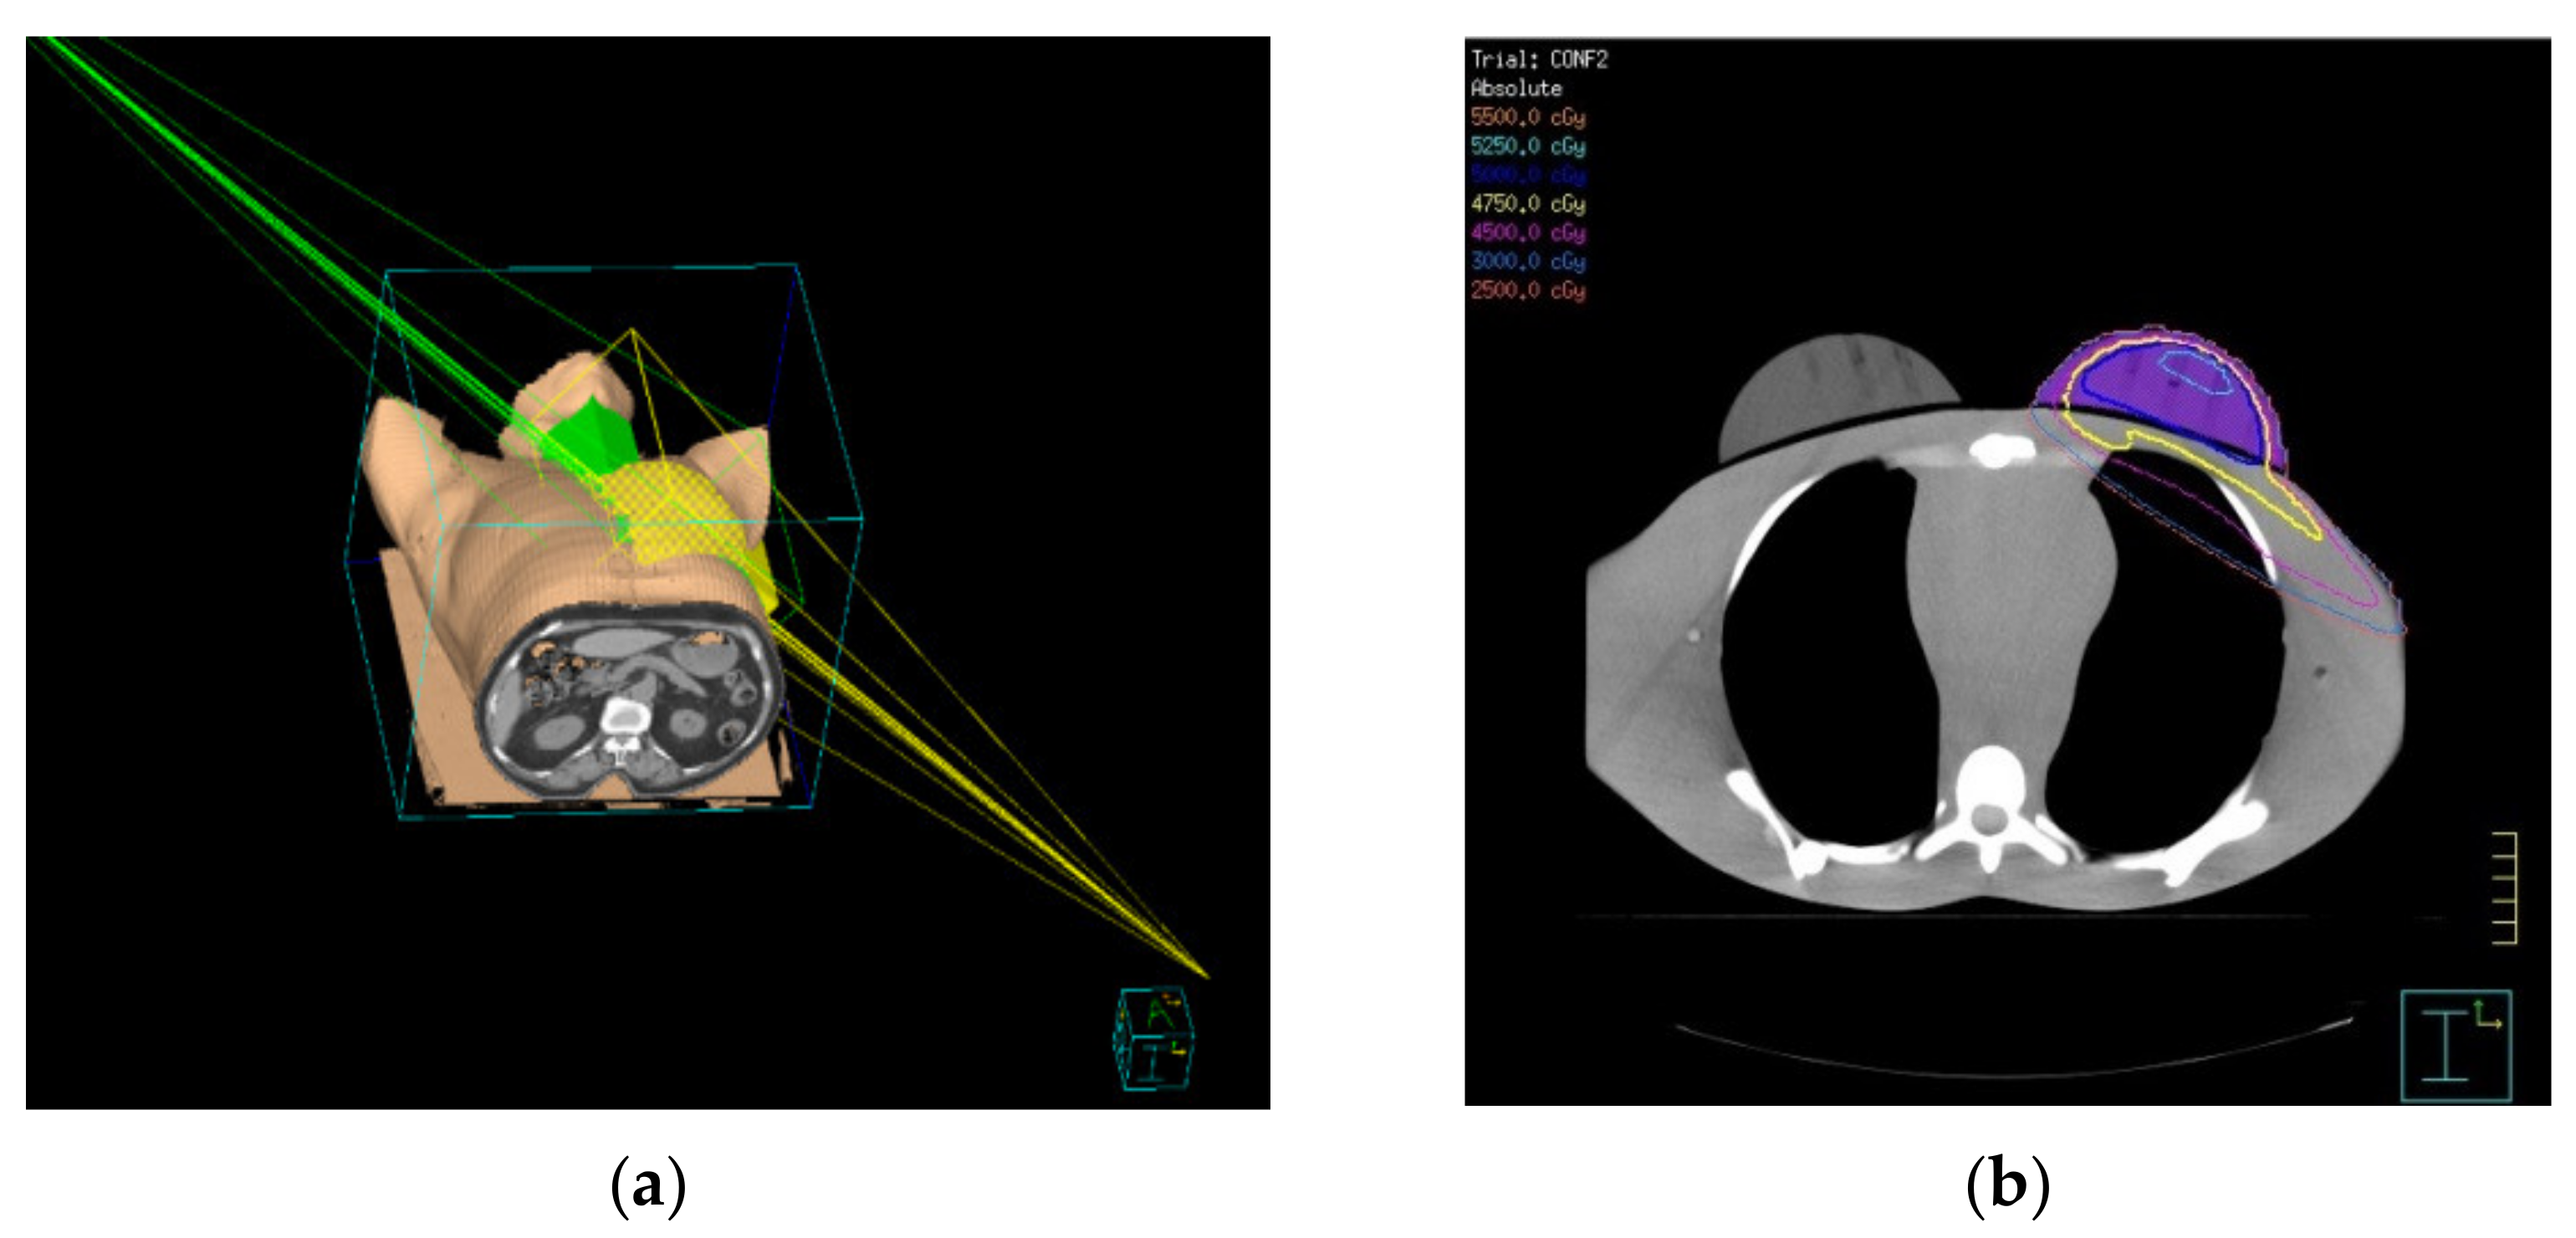

2.3. Tangential 3D-CRT Treatment Planning

2.4. IMRT Treatment Planning